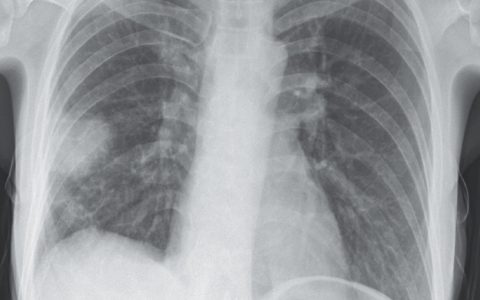

A 66-year-old man is seen in the emergency department after an acute episode of severe hip pain that caused him to fall while walking at home. X-ray shows the presence of a pathological fracture of the pelvis. On questioning, the man reports that in recent months he has felt very fatigued and has been bothered by constant dull pain in his hips, back, and head. A radiograph of his skull is shown in the image. Laboratory studies show a serum calcium of 13.5 mg/dL and alkaline phosphatase of 60 U/L. Which of the following is an additional finding that would be likely in this patient?

该患者患有多发性骨髓瘤。x 线显示颅骨多发性溶解性“穿凿样”病变,这是这种浆细胞恶性肿瘤的经典发现。骨骼的其他区域通常被骨髓瘤细胞浸润,包括椎骨、肋骨和骨盆,这解释了患者在无明显创伤的情况下发生骨折的原因。在碱性磷酸酶水平正常的情况下,溶骨性病变是导致该患者高钙血症的原因。尿蛋白(在这种情况下称为本周蛋白)是多发性骨髓瘤的常见结果,因为肿瘤浆细胞分泌大量免疫球蛋白,轻链易于排泄。免疫球蛋白血清水平过高可导致这些患者发生肾病或淀粉样变性。